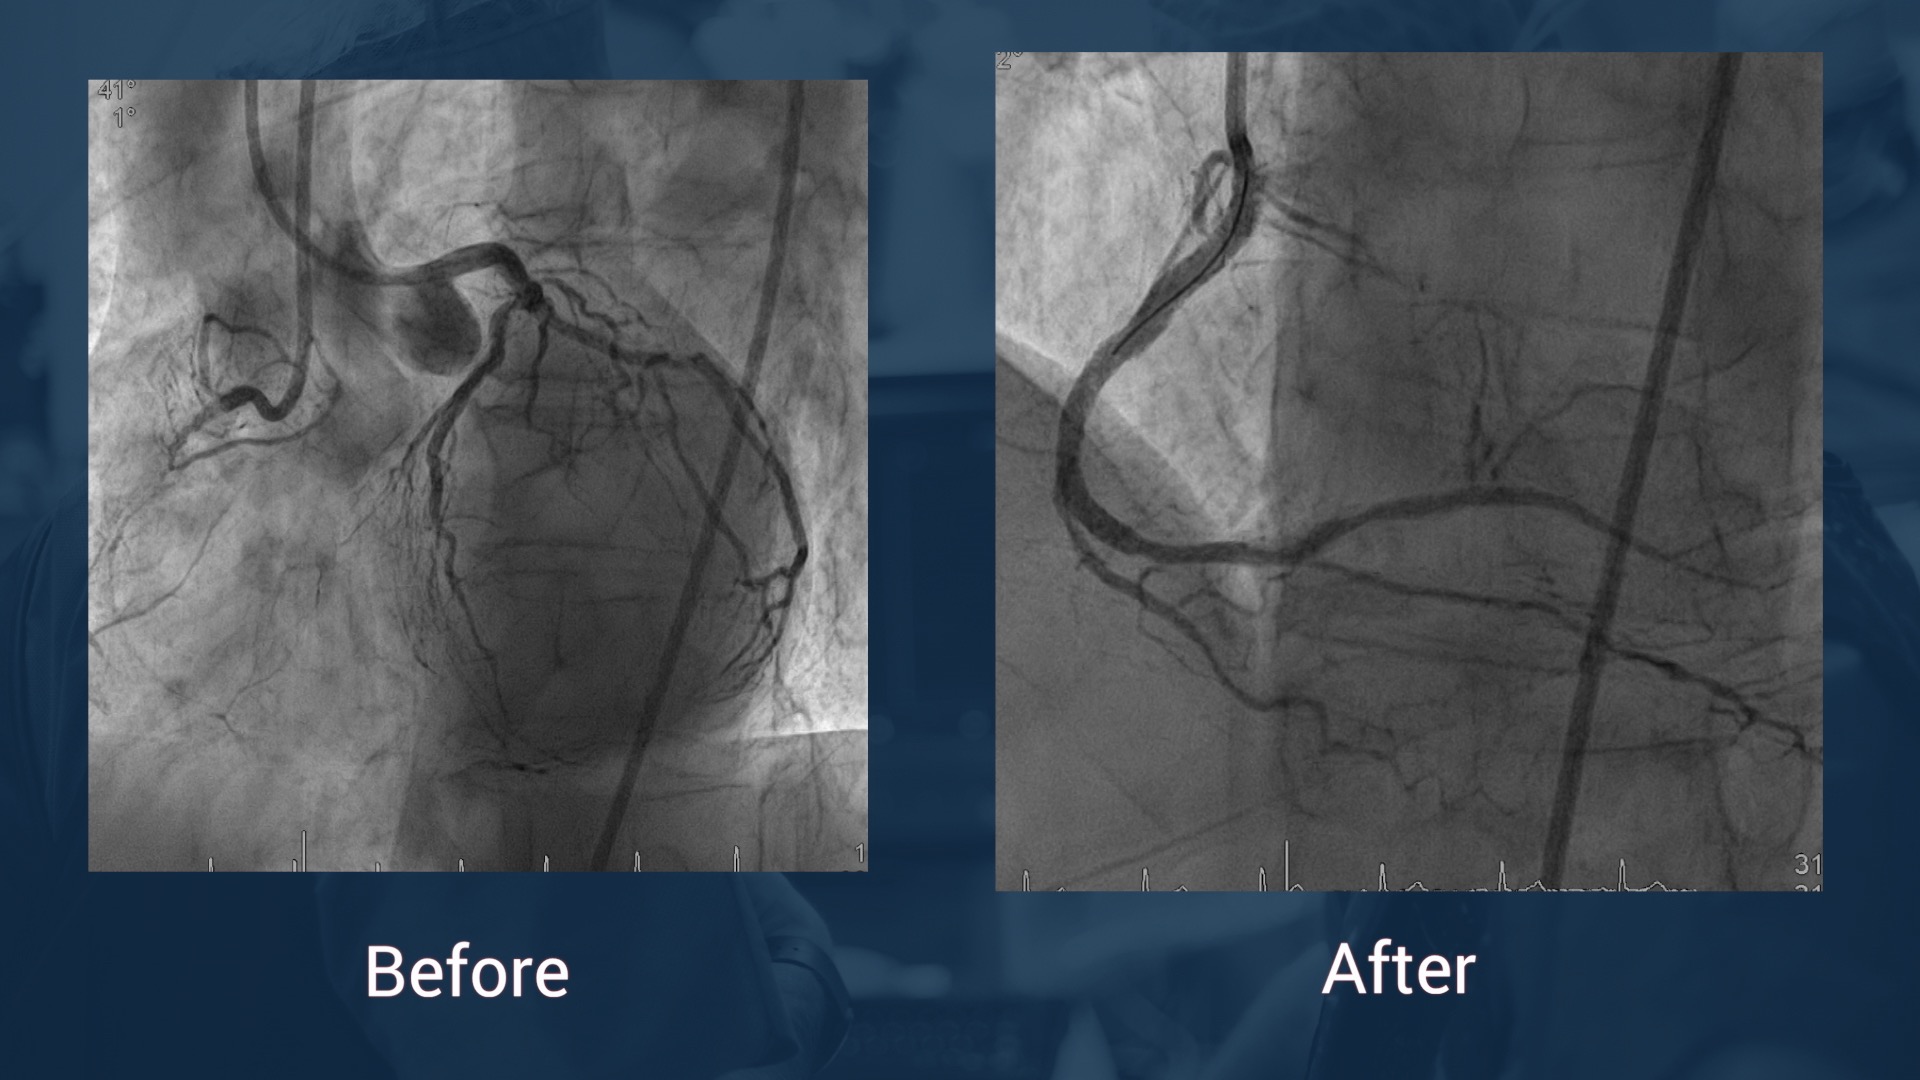

CAG 14.7.17: LAD without stenosis, CX without stenosis, in-stent reocclusion of the RCA

J-CTO score: 1

SeQuent® Please NEO / B. Braun

Next generation coronary Drug Coated Balloon to treat vascular stenosis